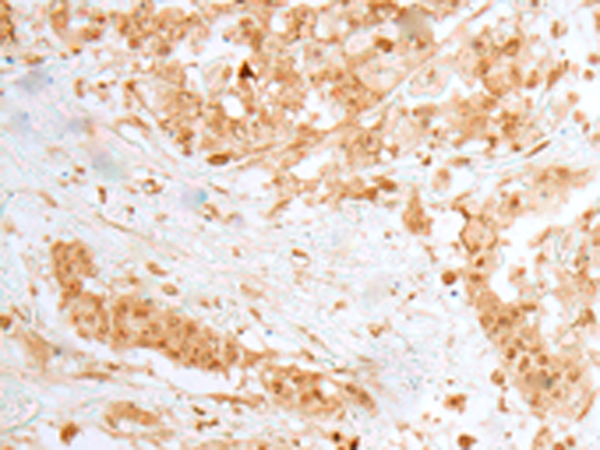

IHC positive control: |

Human thyroid cancer and Human ovarian cancer |

IHC Recommend dilution: |

25-100 |